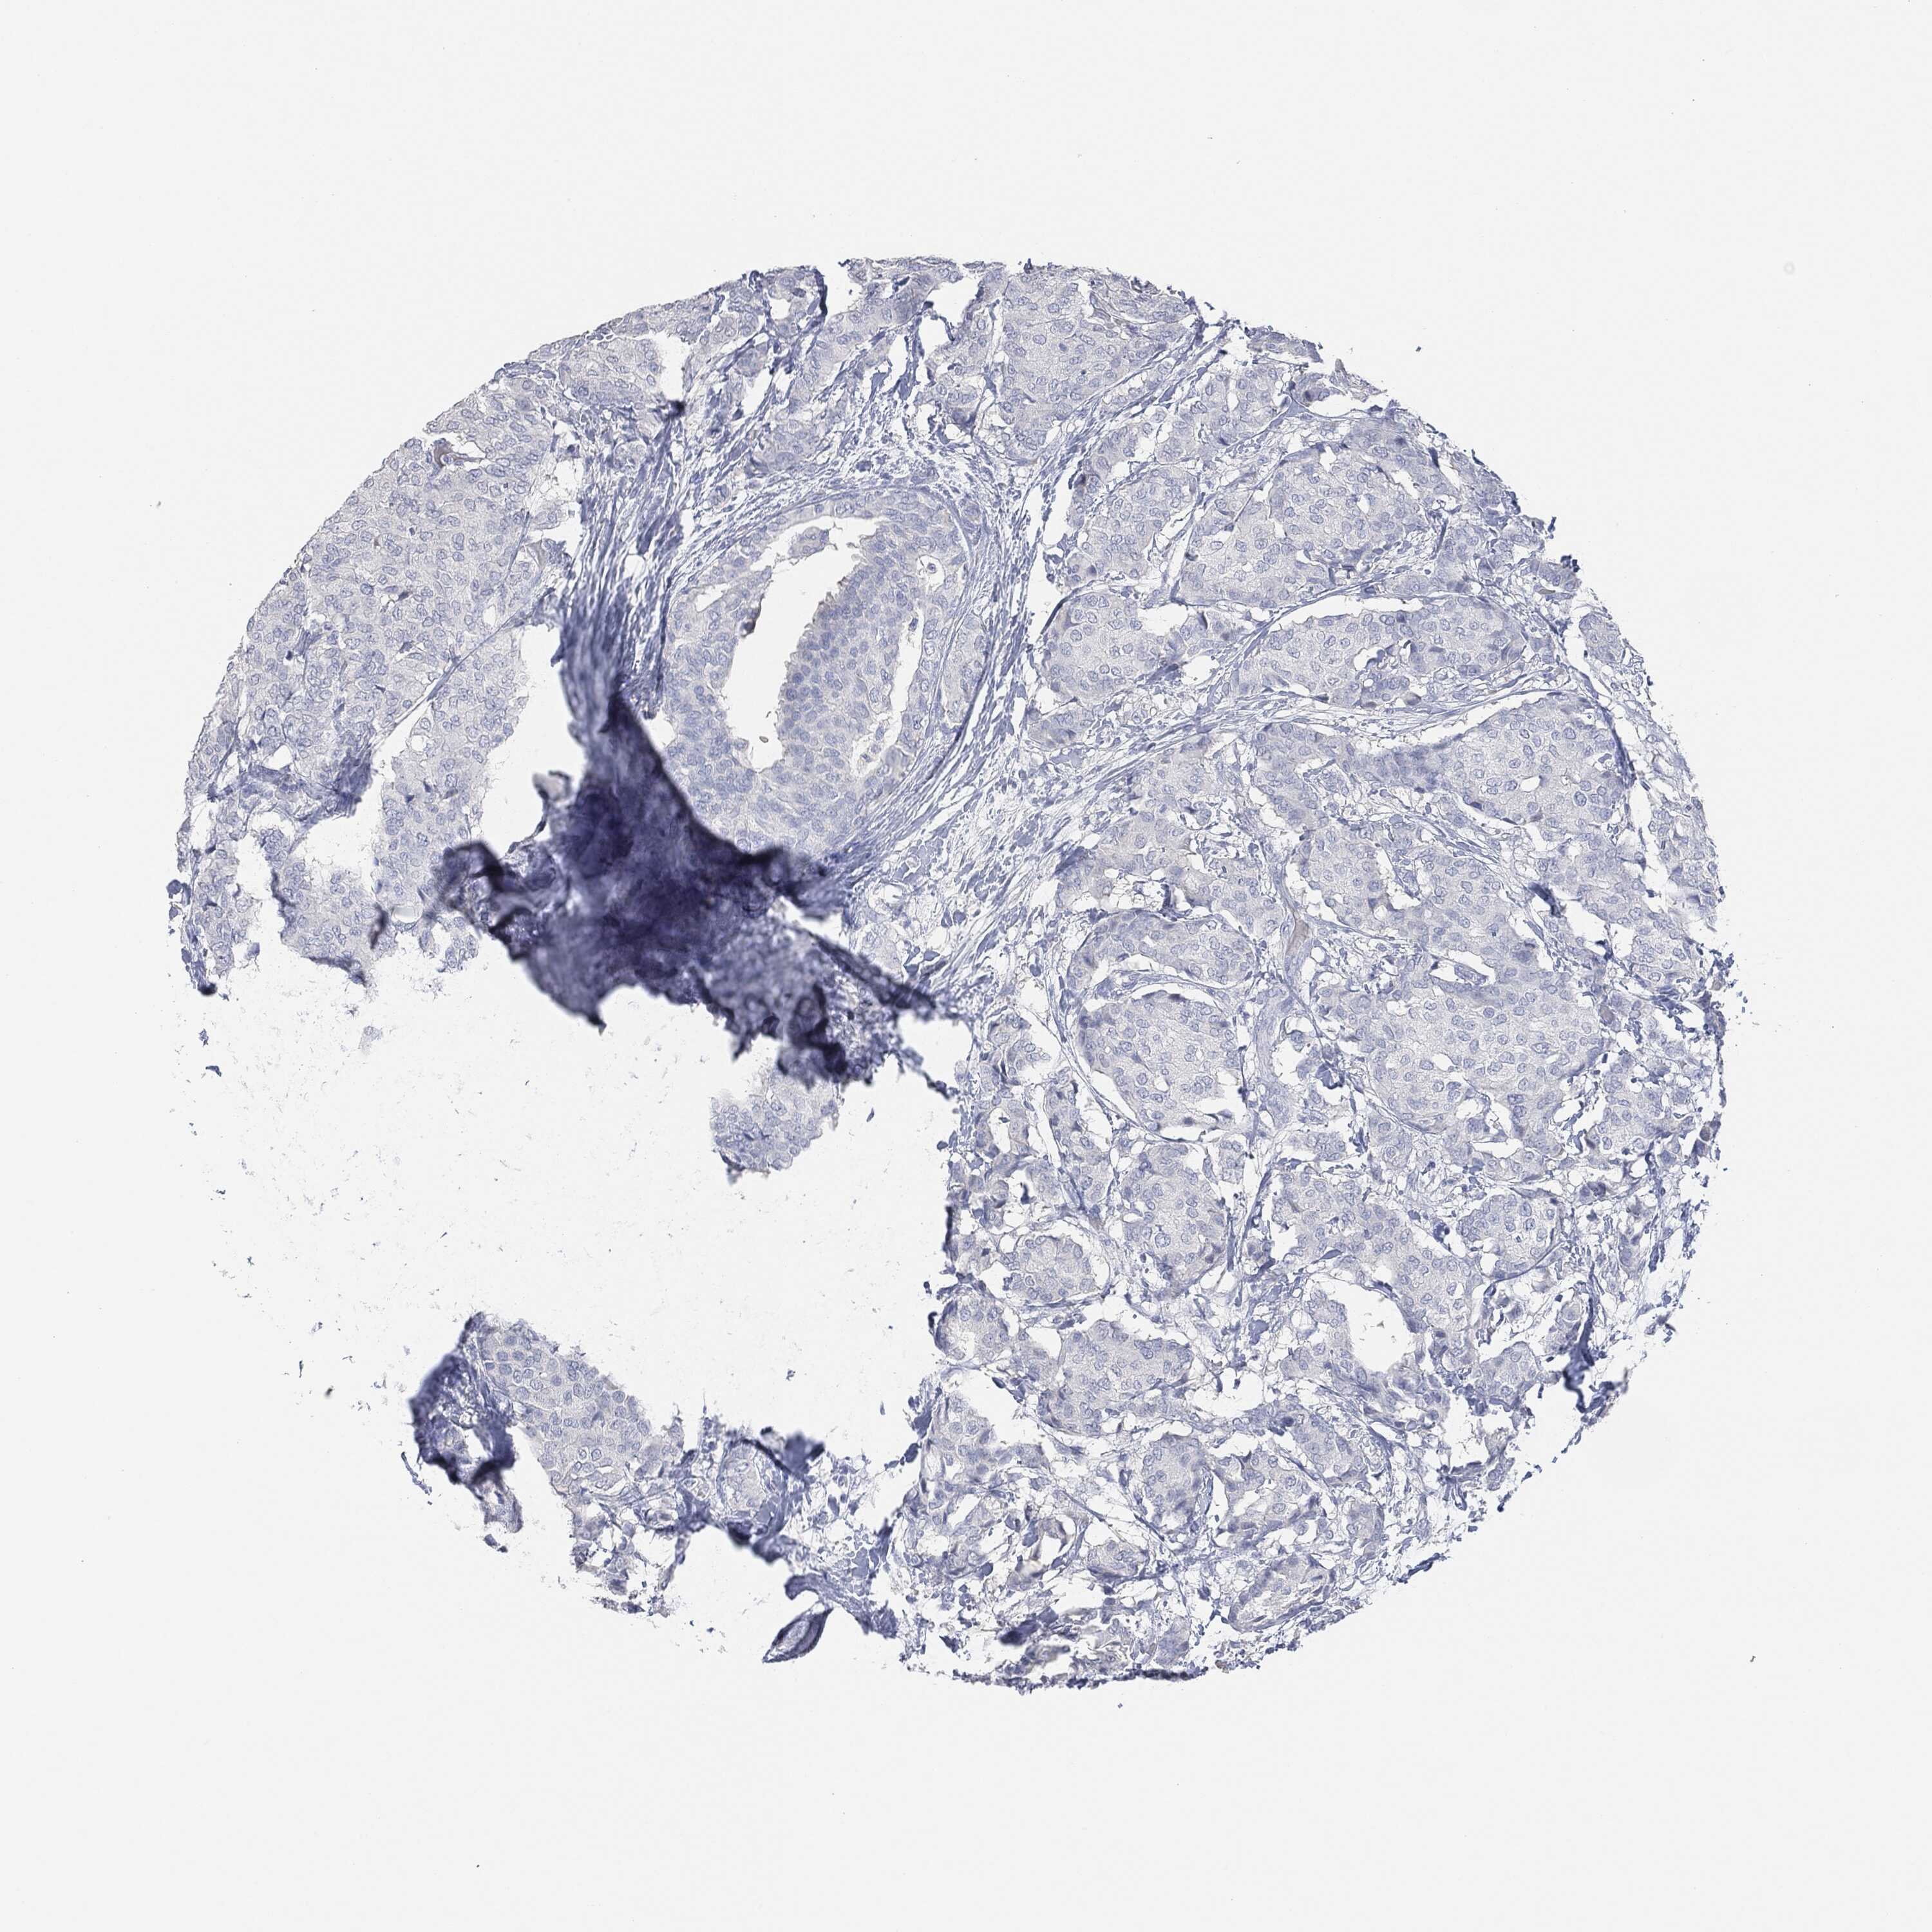

CANCER BREAST CANCER Show tissue menu

BRCA TCGA BRCA VALIDATION PROTEIN EXPRESSION

Breast cancer

Human cancer